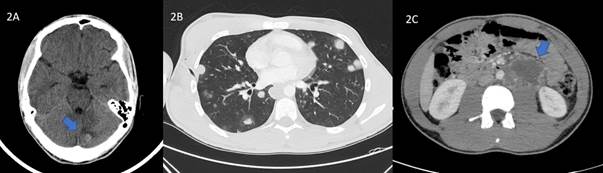

La radiografía torácica de control evidenció una adecuada re-expansión pulmonar. Se ajustó la pauta de insulina alcanzando un adecuado control glucémico; sin embargo, el paciente persistía con mareos y vómitos. Se solicitó un TAC craneal urgente donde se objetivaron 3 lesiones nodulares hiperdensas en la región frontal, occipital y cerebelosa izquierdas, sin edema ni efecto de masa, sugerentes de metástasis (Figura 2A). Posteriormente, se re-exploró al paciente observando una pequeña lesión ulcerada con discreto sangrado en el cuero cabelludo. El paciente lo identificó como un “grano” que había notado desde hacía una semana aproximadamente. Se tomaron biopsias de dicha lesión que informaron de la presencia de células grandes con núcleo vesiculoso atípico y amplio citoplasma con numerosas células multinucleadas intercaladas (sincitio) así como extensas áreas de hemorragia y numerosas mitosis, concluyendo el diagnóstico de metástasis de coriocarcinoma. Como parte del estudio de extensión, se realizó un TAC tóraco-abdominal donde se apreció un importante conglomerado adenopático retroperitoneal (Figura 2B y 2C). El diagnóstico final fue de coriocarcinoma testicular metastásico con afectación pulmonar, cerebral y adenopática.